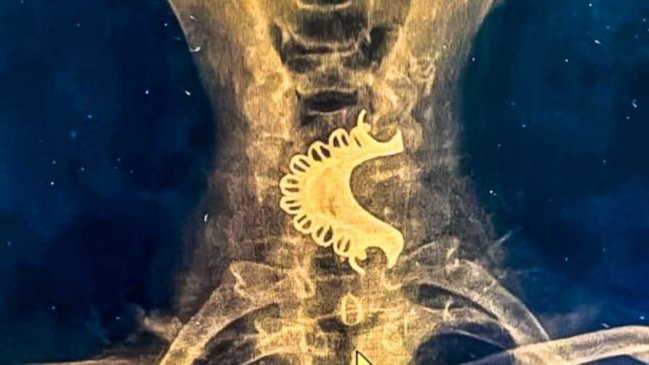

Un hombre de 81 años fue operado de urgencia luego que se tragó su dentadura postiza por accidente durante un episodio epiléptico, en Perú.

Según dieron a conocer los medios locales, el hombre acudió a un centro asistencial tras presentar dolor y dificultades para respirar. Tras realizarle una radiografía cervical, los médicos descubrieron que la dentadura postiza estaba alojada en la hipofaringe, ubicada en la parte inferior de la garganta, la cual permaneció durante cuatro días ahí.

Debido a la gravedad del caso, el paciente fue trasladado a un hospital cercano, donde se decidió realizarle una endoscopía digestiva alta en sala de operaciones para retirar el cuerpo extraño.